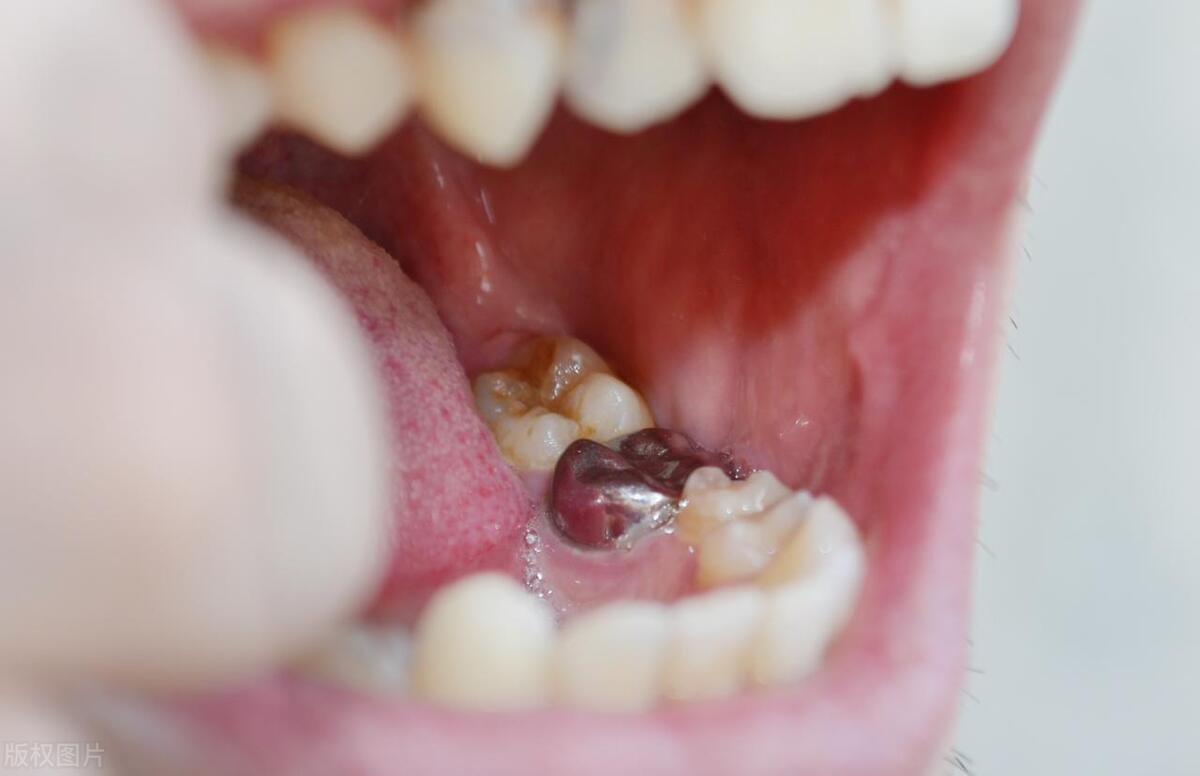

在亲吻时,口腔中的细菌有可能被传播到对方的口腔中,从而增加了口腔感染的风险。细菌的传播可能导致口腔炎症、口臭、牙龈问题以及龋齿和牙周疾病等口腔健康问题。特别是如果其中一方患有口腔疾病,如龋齿或牙周炎,亲吻可能会加速疾病的传播。

龋齿和牙周疾病的风险增加

亲吻时口腔中的细菌可以传播到对方的口腔,这些细菌中可能包含致龋菌和牙周病菌。如果其中一方患有龋齿或牙周疾病,通过亲吻,细菌将进一步扩散并增加对方患病的风险。因此,亲吻时,特别是有牙齿问题的人,应该格外注意口腔卫生,并及时治疗和控制牙齿疾病。